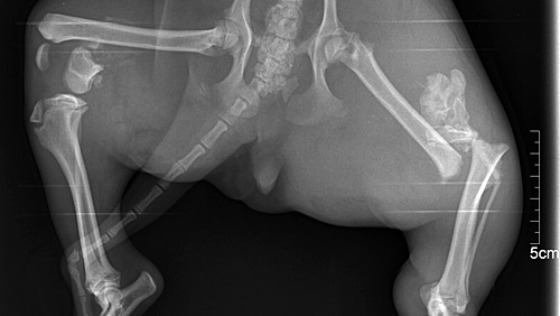

Kochani, Lusia śle Wam kolejne pozdrowienia, ze swojego domu. Sunia czuje się wyśmienicie i choć nie ma jednej łapki, radzi sobie doskonale. To Wasza zasługa.

Mała Lusia, zwykły Burek jakich tysiące. Ale miała dom i liczną rodzinę, której pilnowała. Kochała ją całym swoim serduszkiem i po swojemu się o nich troszczyła. Codziennie rano witała ich uśmiechniętą mordką i wesoło merdającym ogonkiem. Dla nich żyła. Byli całym jej światem. Byli...